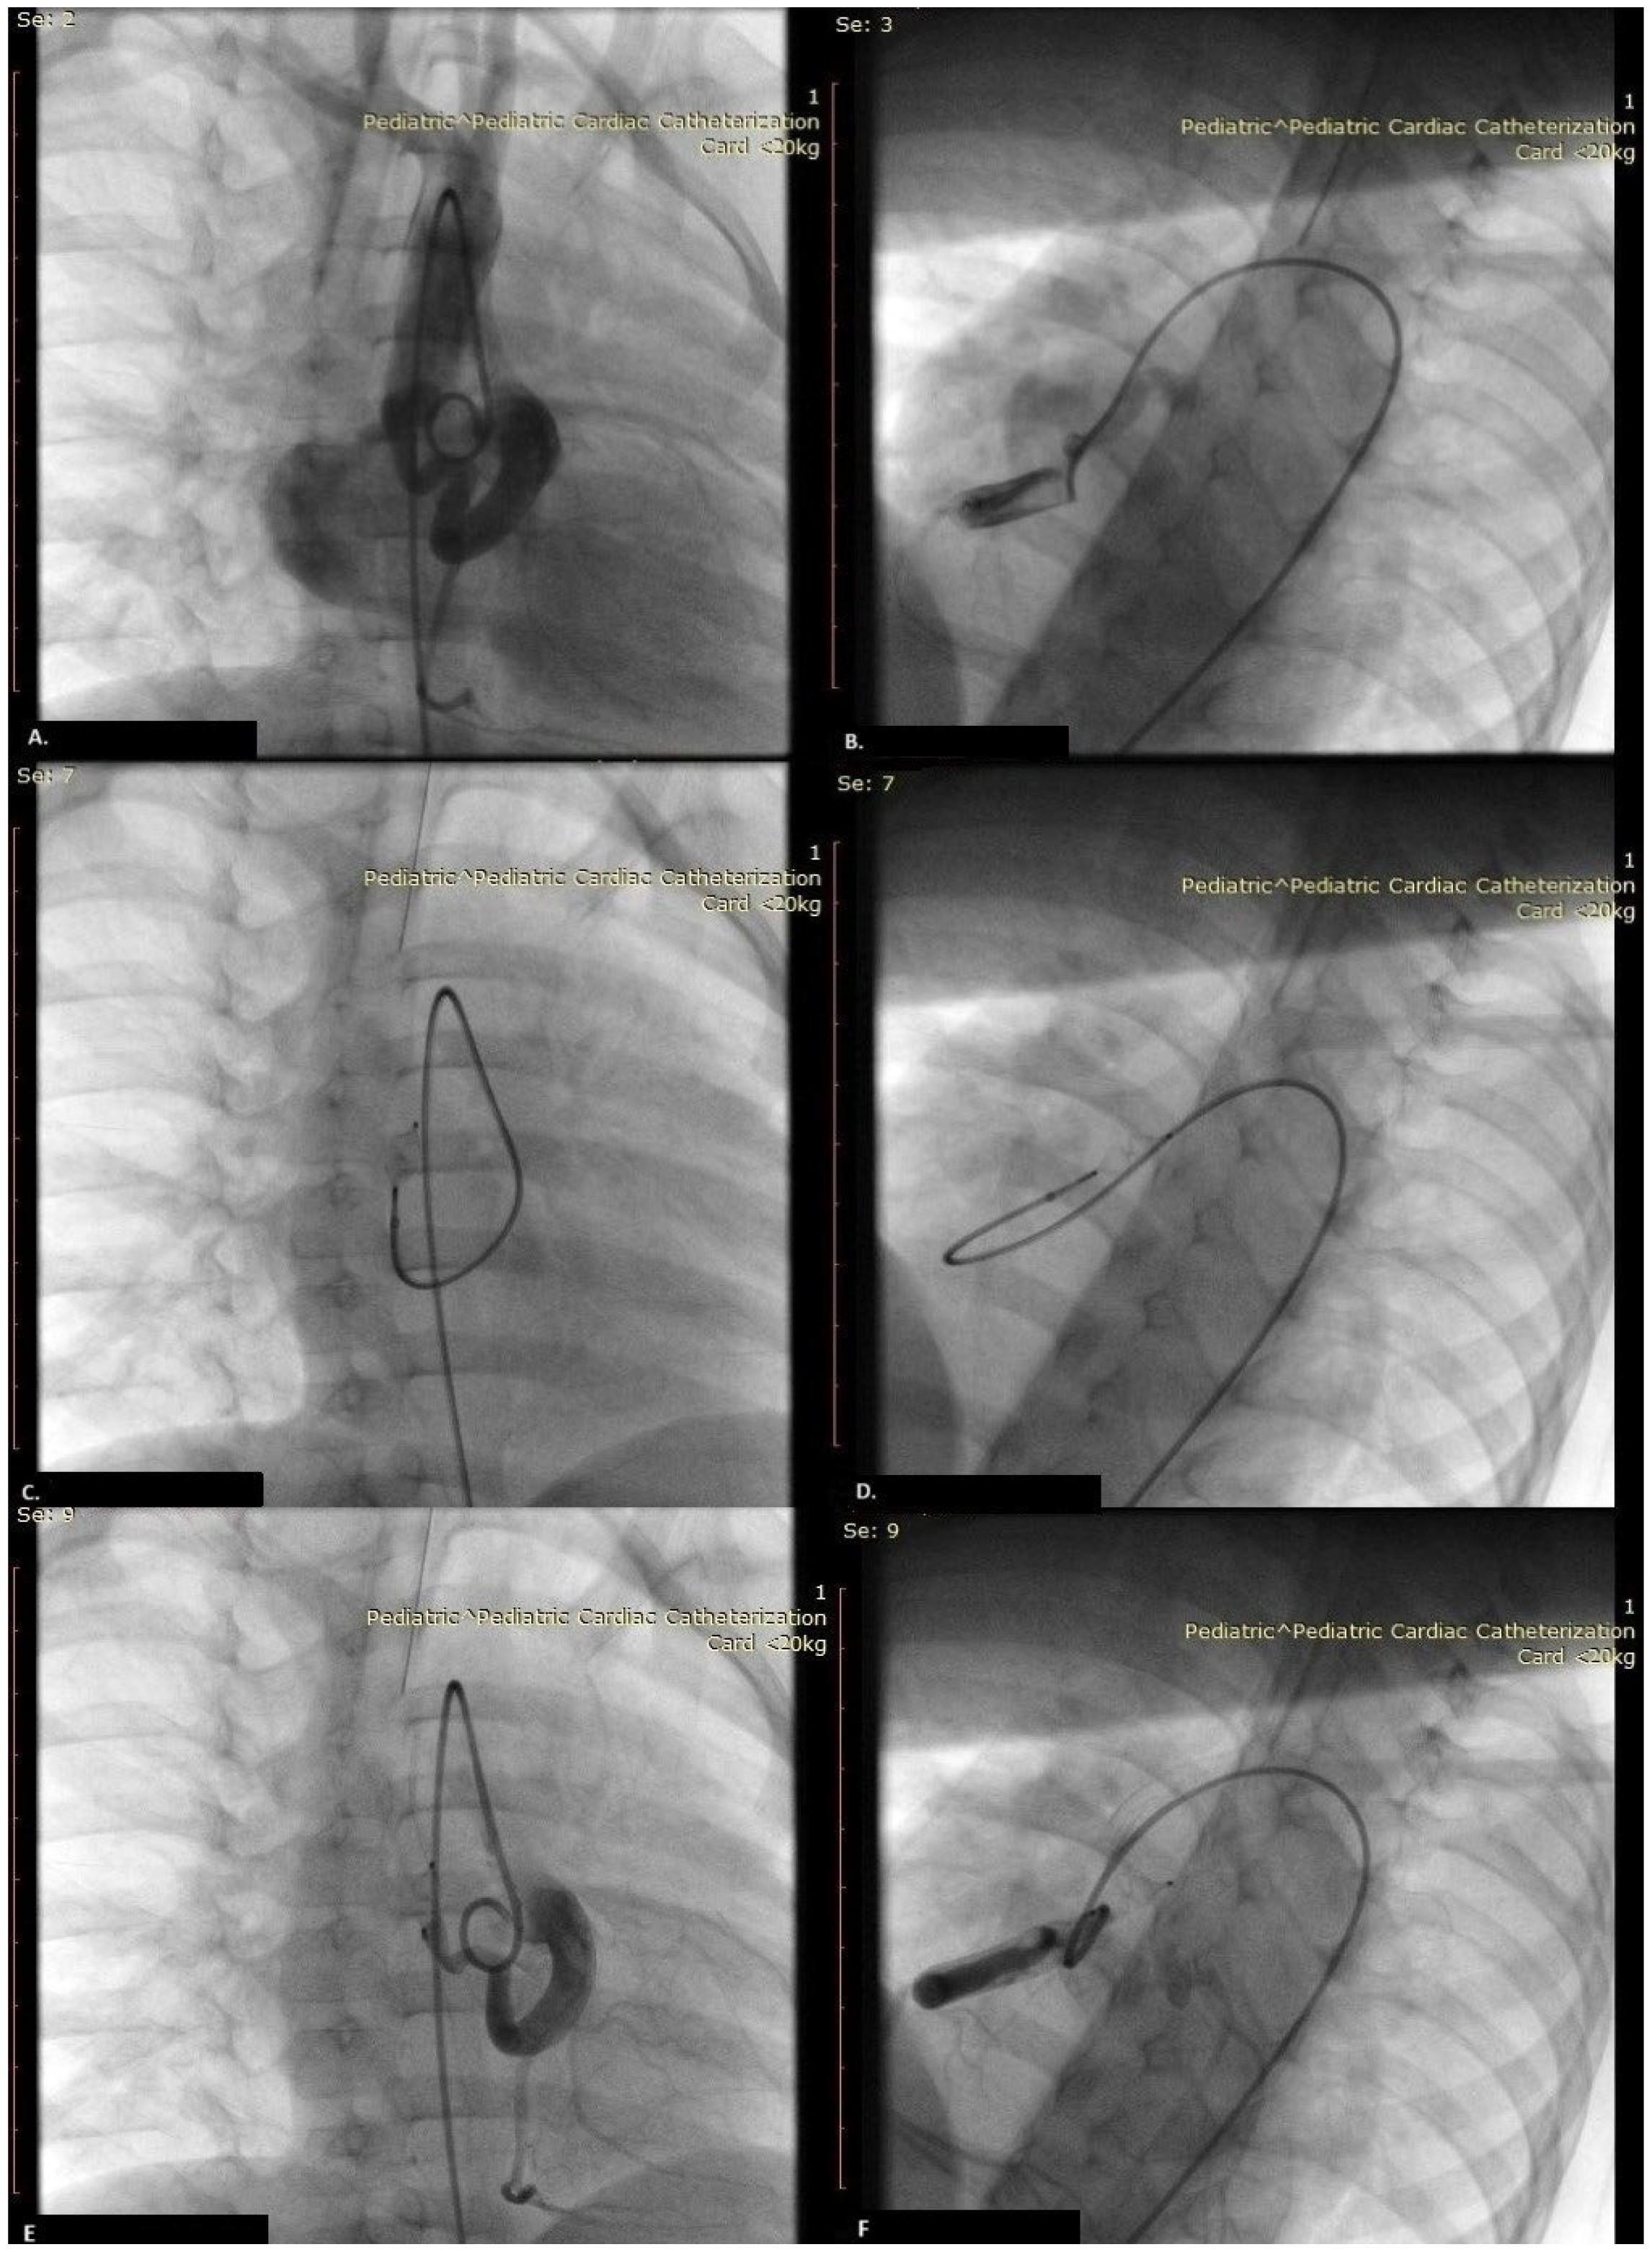

2. Case Report